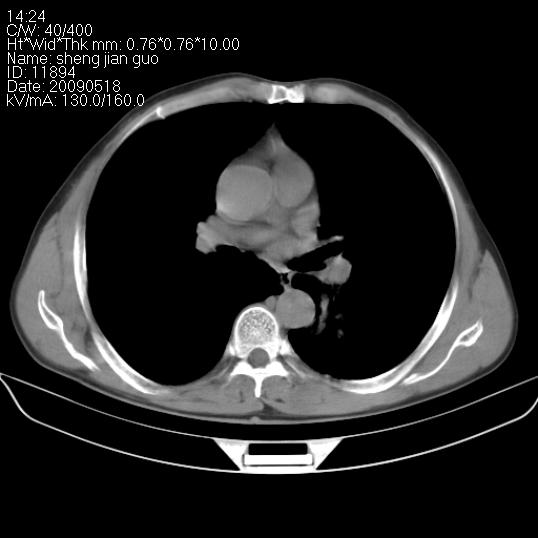

以下是引用zjzjr在2009-5-19 17:25:00的发言:[br]支持楼主考虑,另左肺下叶阻塞性炎症。

以下是引用zhao_bin2008在2009-5-19 17:48:00的发言:[br]支持左肺下叶周围型肺癌并阻塞性肺炎。

以下是引用杀毒软件在2009-5-19 17:36:00的发言:[br]支持楼主

以下是引用zsl6918在2009-5-20 7:10:00的发言:[br]左侧中心型肺癌!